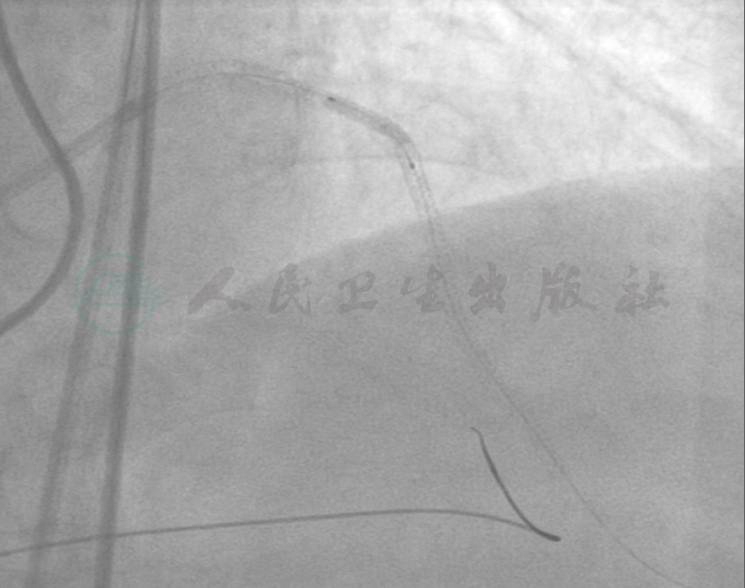

一个月后行左冠PCI。考虑到LCX为中段闭塞,开通可能性大,因此先尝试开通LCX,并且考虑到RCA经间隔支对LAD和LCX提供了良好的侧支循环,遂采用前向结合逆向技术。选用右侧及左侧股动脉途径,保证足够的支撑力。右冠选择6F AL1.0指引导管,左冠选择6F EBU 3.5指引导管,选用Asahi Sion导丝在Asahi Corsair导管支持下经RCA远段侧支循环将导丝进入LCX侧支血管,但未能够进入LCX远段(图5),换用Runthrough NS导丝进入微导管成功进入LCX-OM远段,但不能通过LCX闭塞段,改用Pilot 50导丝后进入假腔(图6)。改正向技术,左冠在Finecross微导管支持下,用Pitlot 50成功通过LCX近中段闭塞病变处进入LCX远段(图7),以GOODMAN 1.3mm×10mm和2.0mm×15mm球囊预扩张LCX远段到近段病变(图8),发现LCX中段病变处出现造影剂渗漏,遂用2.0mm×15mm球囊以5atm压迫造影剂渗漏处约30分钟(图9、图10)。

图6 换用Runthrough NS导丝进入微导管成功进入LCX-OM远段,但不能通过LCX闭塞段,改用Pilot 50导丝后进入假腔